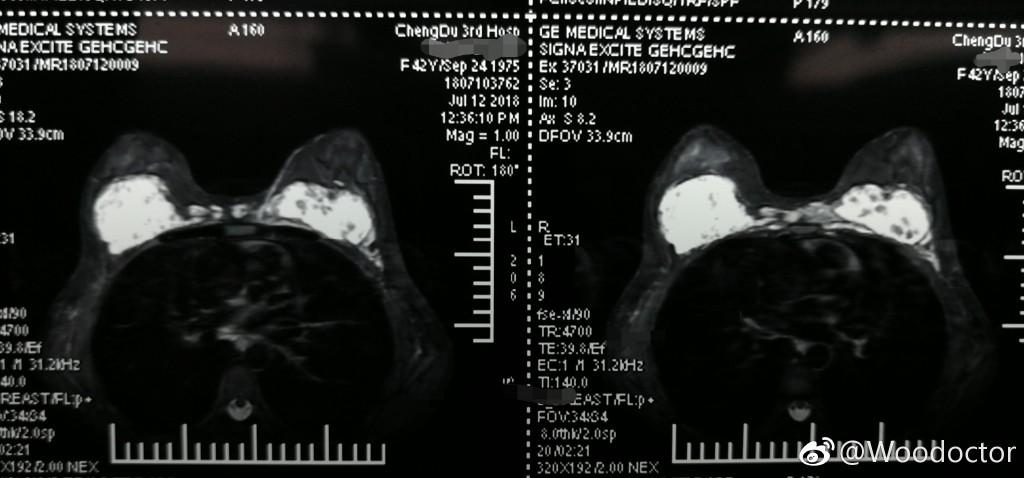

张女士注射的隆胸材料已转移至两胸之间